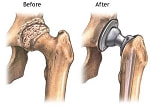

人工関節置換術

●人工関節置換術のメリット

薬物療法やリハビリテーションを行っても病気がよくならず、ひざや股の関節破壊が進み、歩行が困難になっている人にとって、人工関節置換術は救いの道になります。再び歩けるようになるからです。

動く機能も改善され、行動範囲が広がりますので、生活の質(QOL)の向上にもつながります。また、傷んだ部分を改修しますので痛みもとれます。リウマチ患者にとってもっとも心配な「寝たきり」になることを予防することもできます。

●進む技術、素材、形

かつて人工関節は、耐用年数が10年ほどでしたので、摩耗してしまうと新しいものととりかえる再手術が必要になりました。そのため人工関節置換術はなるべく先送りしたほうがよいということで、60才以上になってから行うことがすすめられました。

しかし現在、人工関節は、摩耗の少ない素材や形が開発されて耐用性が飛躍的に伸び、半永久的になっています。また手術法も、より負担の少ない低侵襲性の手術法が開発されています。20代くらいの若い患者さんでも、必要な場合は置換術を受け、運動機能を高めたほうがよいという考えになっています。

●行われる部位

上半身ではひじ下半身ではひざと股でよく行われ治療成績もすぐれています。